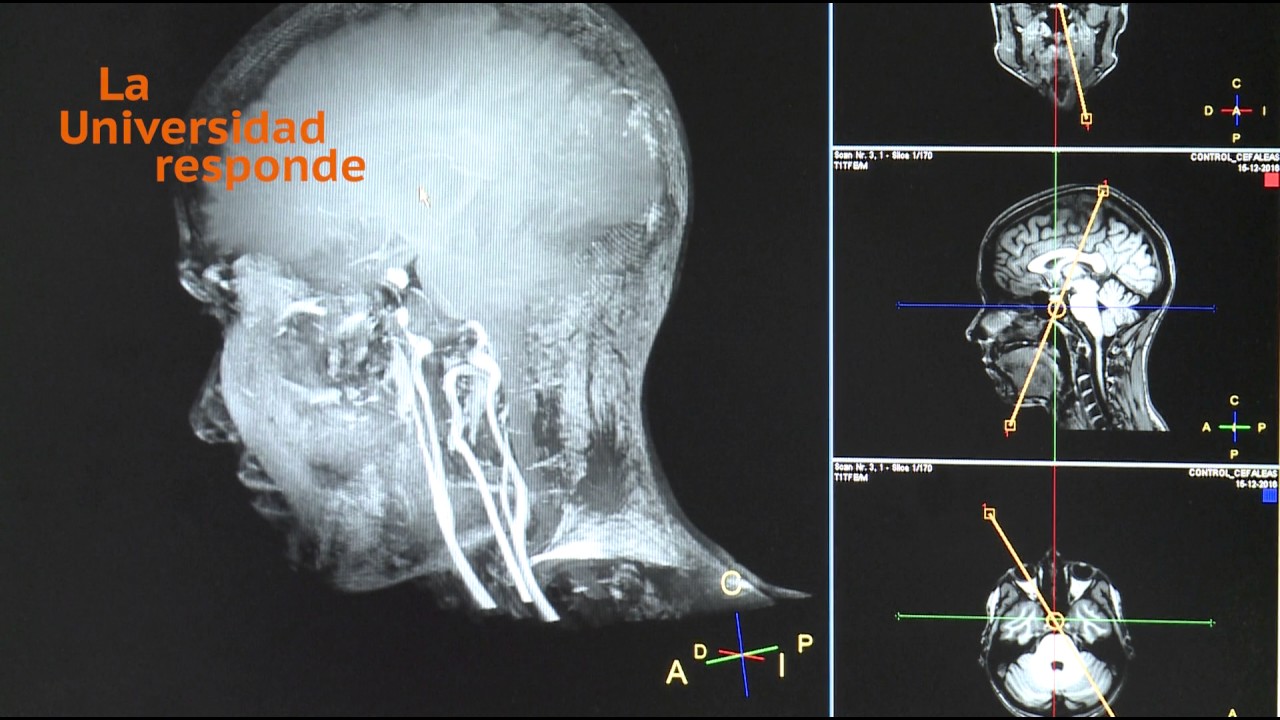

Para empezar, es crucial entender qué es una resonancia magnética (RM). A diferencia de una radiografía, que utiliza rayos X, la resonancia magnética emplea imanes y ondas de radio para crear imágenes detalladas de los órganos y tejidos de tu cuerpo. Es un poco como tomar una foto de cada rincón de tu casa, pero en lugar de usar una cámara, usas tecnología avanzada. Es no invasiva, lo que significa que no hay necesidad de hacer cortes y siempre tiene el objetivo de encontrar problemas sin causar más daño.